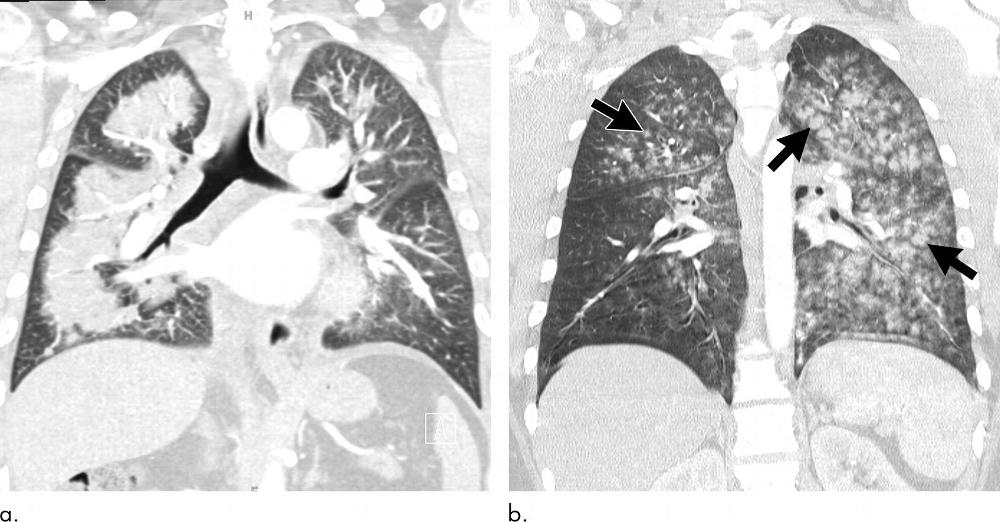

Figure 12. Images show multiple episodes of electronic cigarette or vaping product use–associated lung injury due to repeated vaping of nicotine with mint flavoring in a 51-year-old woman. Bronchoalveolar lavage (BAL) fluid showed numerous foamy lipid-laden macrophages with positive Oil-Red-O lipid staining. (a) CT in September shows organizing pneumonia pattern with scattered areas of ground-glass opacity with subpleural sparing. Workup for infection was negative, and patient was started on steroids and improved. (b) Two months later, patient returned to emergency department with dyspnea and fever. CT image shows more extensive ground-glass opacity with areas of lobular and subpleural sparing. Interlobular and intralobular septal thickening is present, creating “crazy paving” pattern. (c) Although patient’s BAL fluid showed many lipid-laden macrophages, soft-tissue image shows no evidence of intraparenchymal fat attenuation, a common finding in lipoid pneumonia. Patient’s condition deteriorated, and she was intubated and started on steroids. (d) Ten days after initiation of steroids, ground-glass opacity has improved but persists. Patient’s condition was complicated by aspiration pneumonia and bilateral lower-lobe collapse.

High-res (TIF) version